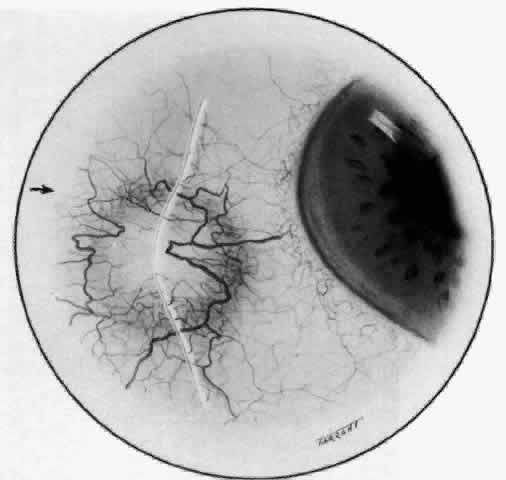

With the increasing use of anterior segment fluorescein angiography in the early detection of severe necrotizing disease of the sclera, it is necessary to have an understanding of the normal anatomy of the vasculature of the anterior segment of the eye.3–5 The blood supply to this region is enormous, being derived from the anterior ciliary arteries, but with extensive collateral arterial anastomoses to the posterior ciliary arteries at the root of the iris (Fig. 1). The anterior system is readily visible with the slit lamp and by anterior segment fluorescein angiography, especially if the eye is inflamed, and its recognition is of vital importance in the differentiation of episcleral and scleral conditions. The separation and displacement of these vascular layers give the most important clinical clues to the site and, hence, the severity of the inflammation. On slit lamp examination, three layers of vessels are readily visible. The conjunctival plexus, which is the most superficial layer of vessels, can be moved over the underlying structures. The superficial episcleral capillary plexus (Fig. 2) is a radially arranged series of vessels lying within the parietal layer of Tenon's capsule. The vessels in this layer anastomose at the limbus with the conjunctival vessels, with other members of the same plexus, and with the deep plexus. The deep episcleral capillary network (see Fig. 2) is closely applied to the sclera in the visceral layer of Tenon's capsule. The vessels anastomose freely with each other, forming a syncytium. The large vessels to and from the intrascleral plexus traverse the episclera near the insertions of the muscles. The conjunctival and superficial episcleral vessels can be blanched with 1:1000 epinephrine or 10% phenylephrine, but the deep vessels are affected slightly. This is of considerable assistance when attempting to differentiate deep and superficial inflammation.

Fig. 1. Anterior view montage of a cynomolgus monkey ocular casting with Tenon's and episcleral vessels removed. The anterior ciliary arteries (ACA) arborize at the limbus and interconnect via their lateral branches to form the episcleral circle. (CM, ciliary muscle capillary bed; CV, choroidal veins; EC, episcleral circle. (Original magnification, X20). (Morrison JC, van Buskirk EM: Anterior collateral circulation in the primate eye. Ophthalmology 90:707, 1983)

Fig. 2. The normal relationships of the capillary networks that can be seen with the slit lamp are a conjunctival (easily mobile) network, a superficial episcleral network in the parietal layer of Tenon's capsule, and a deep episcleral plexus closely applied to the sclera. These relationships are much more obvious in inflamed eyes (see Figs. 13, 14, and 30). (Watson PG, Hayreh S, Awdry P: Episcleritis and scleritis. Br J Ophthalmol 52(3):278– 279, 1968)